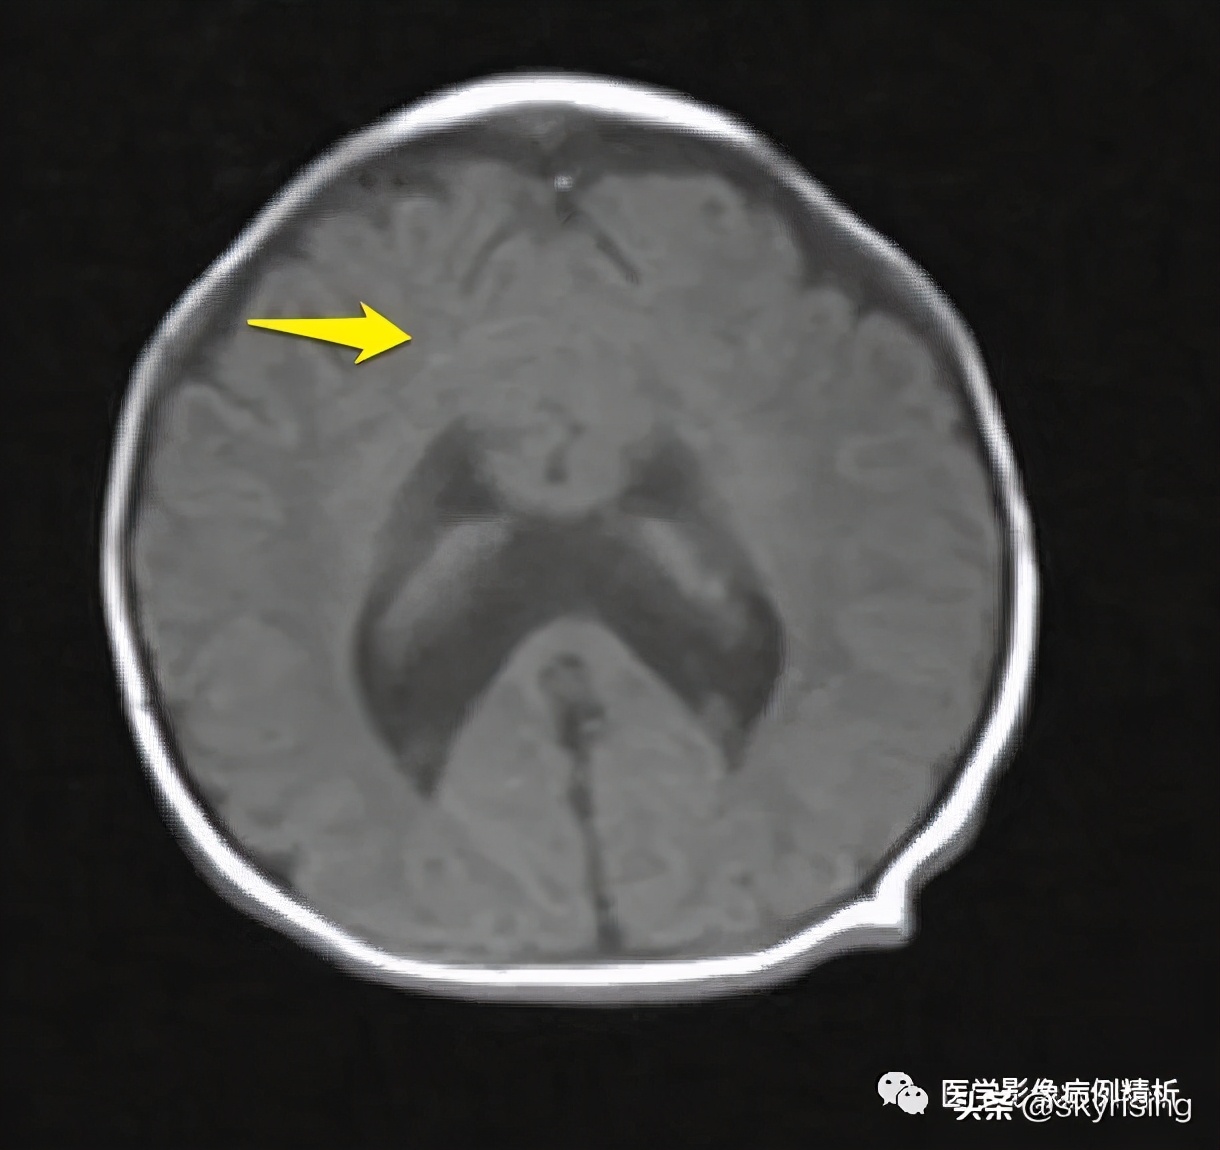

T1WI轴位像:黄色箭头所示可见大脑前纵裂缺如,双侧额叶脑实质融合,胼胝体膝部未见显示。透明隔缺如,双侧侧脑室融合呈蝙蝠翼样改变。侧脑室额角未见显示,体部平行于矢状线,后角失去张力、变尖。

黄色箭头所示为大脑前动脉单支血管影,被推移至融合脑实质前。枕角形态尚可。双侧额部蛛网膜下腔增宽,见细带状液体信号,提示硬膜下积液。